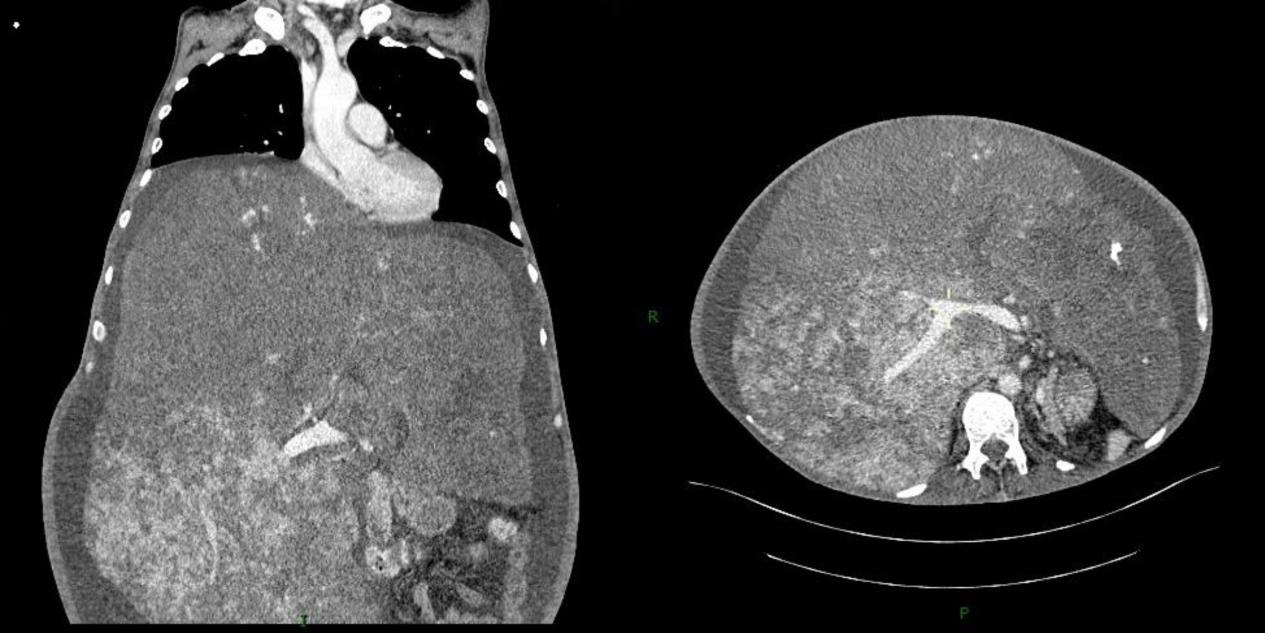

患者男,57岁,2020年11月30日因脑出血就诊于当地医院,治疗期间腹胀突然加重,随后转诊至本院。患者有轻度腹胀10余年病史,从未做过任何相关检查,也未服用过任何药物,否认肝炎、结核等病史。入院查体:患者使用气管插管和呼吸机进行辅助通气,全身皮肤黏膜黄染、可见散在瘀斑,严重腹胀,腹部有轻压痛,体格检查及超声检查结果均提示肝下界在前正中线上达脐水平线下8 cm处(图 1),脾脏未触及,双下肢中等程度水肿。实验室检查发现许多异常,包括红细胞2.52×1012/L、血红蛋白82 g/L和血小板63×109/L,白蛋白34.6 g/L,凝血酶原时间15.6 s,活化部分凝血酶时间46.8 s,纤维蛋白原0.62 g/L,D-二聚体31.09 mg/L等。乙肝抗原、丙型肝炎病毒抗体检测均为阴性,血清肿瘤标志物均在正常范围内。超声检查提示肝脏体积巨大,肝脏内探及大小不一的不均质回声团,边界不清。普通CT扫描检查提示:肝脏体积明显增大(约44.06 cm×38.46 cm×10.21 cm),肝叶比例失调,肝实质密度不均。入院3 d后,为了获取明确诊断,对患者的肝脏进行多部位穿刺活检后送病理学检查,诊断结果为:肝海绵状血管瘤(图 2)。该检查导致了腹腔内活动性出血,肝功能急剧下降等意料之外的严重后果。笔者随即对患者行腹腔血管造影及介入栓塞术止血治疗,同时使用药物改善肝功能,患者病情恢复平稳。入院15 d后,由于患者多次血常规检查提示外周血全血细胞减少,又给予骨髓穿刺检查排除血液系统疾病。入院20 d后,我们对患者进行腹部核磁共振扫描来评估病情,但仍未明确诊断。于是又进行腹部增强CT扫描检查,结果提示肝脏体积明显增大,密度不均,全肝弥漫分布片状及斑片状低密度灶,增强扫描病灶未见明显强化,病灶间散在正常强化肝组织,符合弥漫性海绵状肝血管瘤诊断(图 3)。结合所有检查及患者临床表现,患者最终被诊断为弥漫性肝血管瘤病合并卡萨巴赫-梅里特综合征。肝移植被认为是本例患者可以根治性治疗的唯一办法,但考虑到他近期的脑出血病史及身体情况而没有进行手术。笔者给予患者积极的对症治疗,包括使用药物改善肝功能,输注新鲜的冰冻血浆、冷沉淀凝血因子、血小板等。不幸的是,该患者在确诊1个多月后死于多器官功能衰竭。

| 图 3 腹部增强CT检查 |